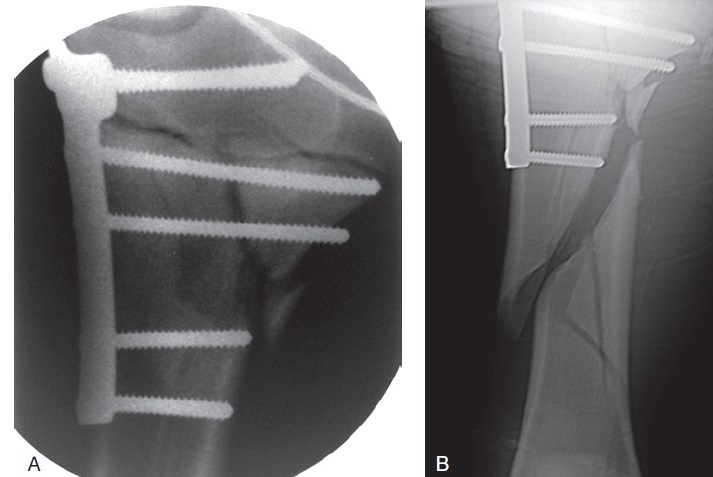

Figure 100-7. (A) A caudocranial intraoperative fluoroscopic view of a proximal tibial physeal fracture repaired with a four-hole T-plate. This fracture was more severe than a routine proximal tibial physeal fracture and required a more involved fixation. The metaphyseal component is comminuted and extends more than half the width of the bone. In addition, there is only one screw that is anchored in healthy bone distal to the comminuted fracture. This fracture probably required two implants and more distal fixation to resist the biomechanical instability the comminution created. (B) The caudocranial follow-up radiograph taken the next day because the foal was non–weight bearing on the limb. A catastrophic bone failure occurred during the night. The fracture initiated at the distal end of the original fracture and spiraled distally, leading to catastrophic failure of the bone. The owner did not want to proceed with treatment and the foal was humanely destroyed.

What is the most common complication encountered with proximal physeal fracture repair?

Fixation failure

Smaller the foal better prognosis Closure of the proximal tibial physis can occur, but it is not a major complication